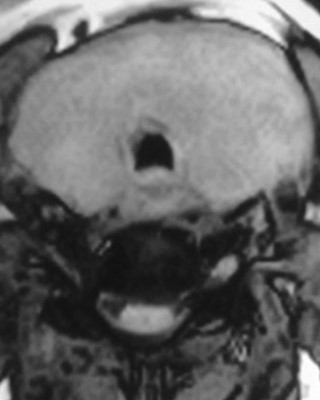

CT — Well-circumscribed nodule in contact with the lower pole of the left thyroid lobe (Courtesy Dr. V. Penopoulos)